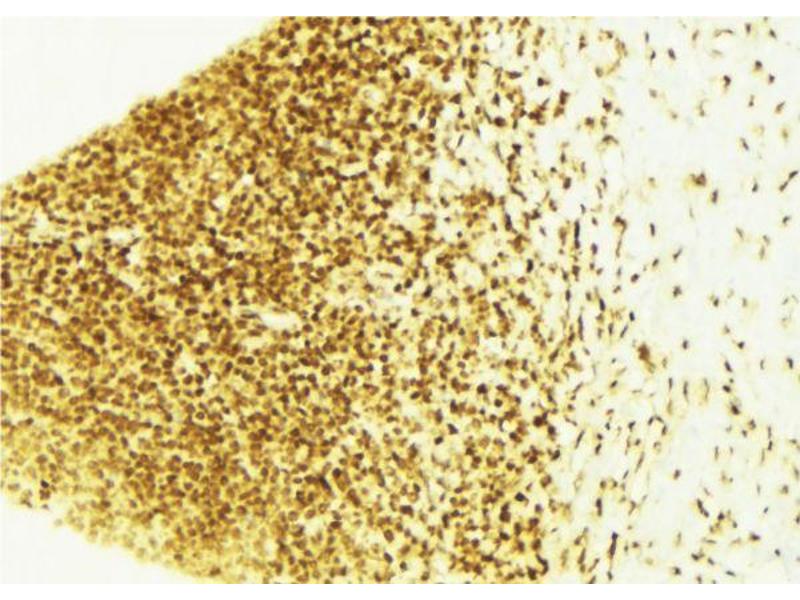

- WB 1:500-1:2000, IHC 1:50-1:200, IF/ICC 1:100-1:500, ELISA(peptide) 1:20000-1:40000